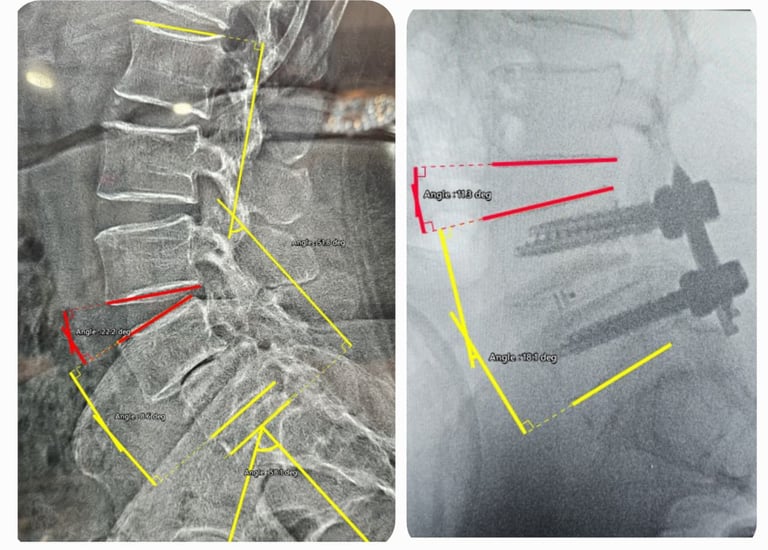

Spine Fusion Surgery MIS TLIF

Stitch-less techniques for faster healing.

Degenerative Scoliosis Correction

Gentle corrections for lasting posture improvement.